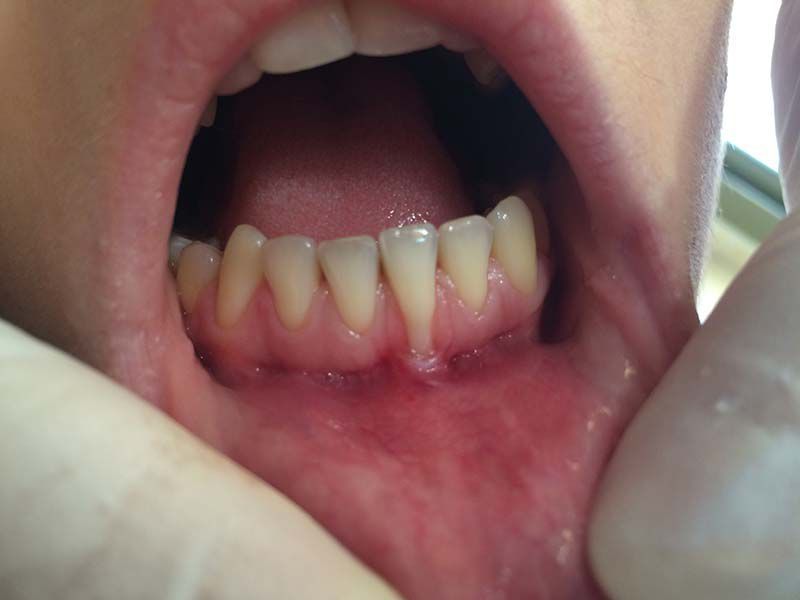

Especialización dedicada al cuidado de las encías. En este caso, se ha realizado un injerto de conjuntivo en el incisivo central inferior